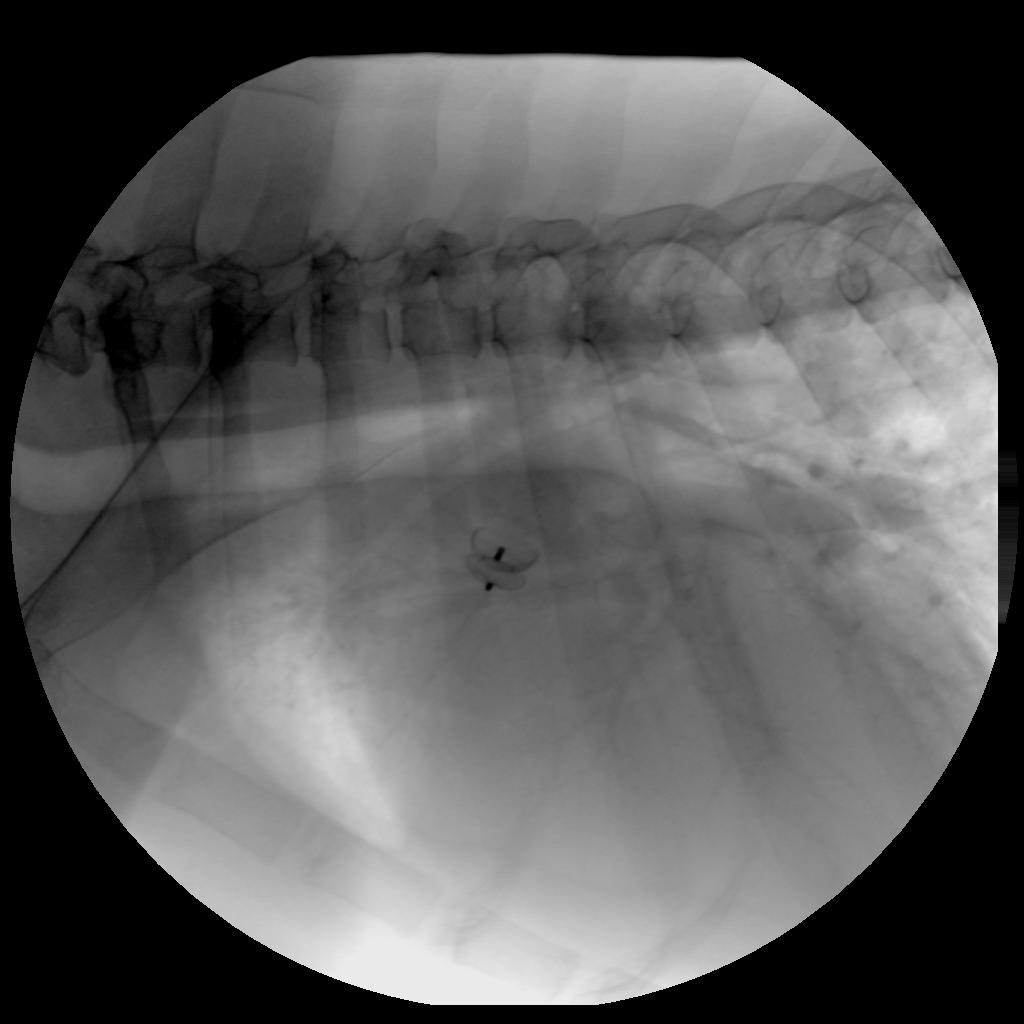

Ultrasound of Mollie’s heart (an echocardiogram) shows high velocity turbulent (green) blood flow from the aorta to the pulmonary artery consistent with a PDA. Angiography (real-time X-rays) shows the location of the PDA and directs a device (ACDO) to the PDA to rapidly close the defect. |

SCN Rescue, recognizing the criteria Mary Price mentioned, decided to go forward with the surgery. Mollie stayed at OSU in Dr. Scansen’s care, scheduled for surgery two days later. The surgery went excellently. A tiny expanding wire mesh, “Canine Duct Occluder,”1 conformed to the shape of the PDA was inserted through the femoral artery in her back right leg. A few hours after surgery, Mollie recovered very well, thumping her tail as her vet student Kristen talked to her. Another ultrasound was done the next morning before SCN Rescue picked her up, and it was determined that the PDA was indeed closed, and the pressures across the aortic valve were already down to the high normal range with no visible SAS found. It is expected that her heart will gradually go down in size with the reduction in blood flow from the PDA closure. She was started on a low dose of Enalapril to help keep the fluid away from her heart.